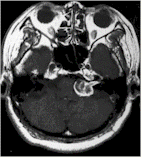

| ・Gamma knife |

Main targeted disease

・Metastatic brain tumor

・Cerebral arteriovenous malformation

・Acoustic neuroma

・NBuroblastoma

・Meningioma |

| Before |

After 3 months |

After 11months |

|

Before |

| Acoustic neuroma |

Metastatic brain tumor |